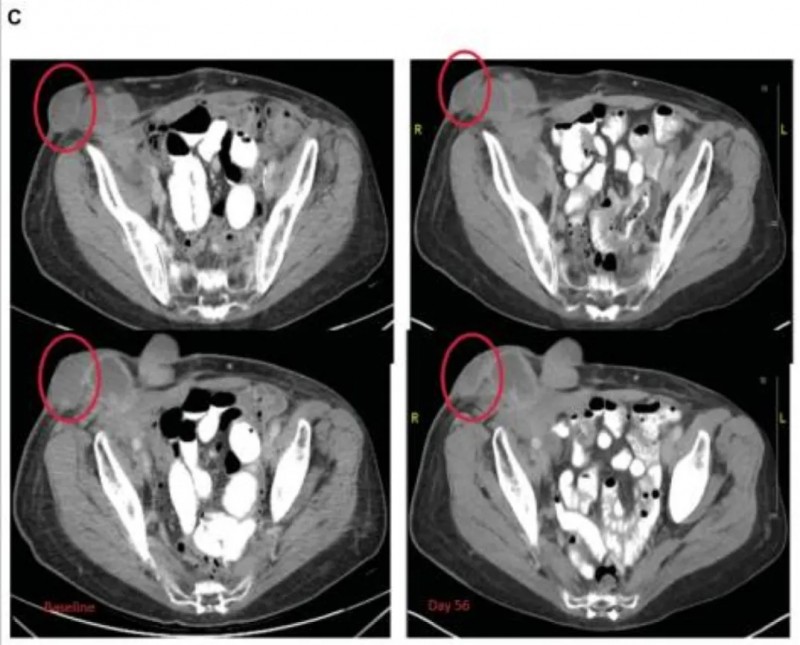

结果显示:疫苗治疗后的效果呈现出持续改善的趋势,治疗前的CT复查显示,患者左下叶病变已缩小至3cm×3cm(详见下图A),左上叶病变直径<1cm,同时存在放射治疗引发的包裹性胸腔积液;疫苗治疗3个月后,左下叶肿瘤进一步缩小至2cm×2.1cm(详见下图B);治疗6个月后,肿瘤体积降至1.5cm×2.3cm(详见下图C),较初始放化疗后的大小缩小30%,且后续趋于稳定,同期患者的胸腔积液减少、局部淋巴结缩小。

值得特别关注的是1例63岁浆液性输卵管/卵巢癌患者:该患者此前已接受过13线全身治疗,虽按RECIST标准其最佳疗效判定为SD,但注射病灶在4次治疗后接近消退,周围未注射的病灶在治疗第4周期也明显变平(详见下图),展现出该疗法在局部病灶控制上的潜力。